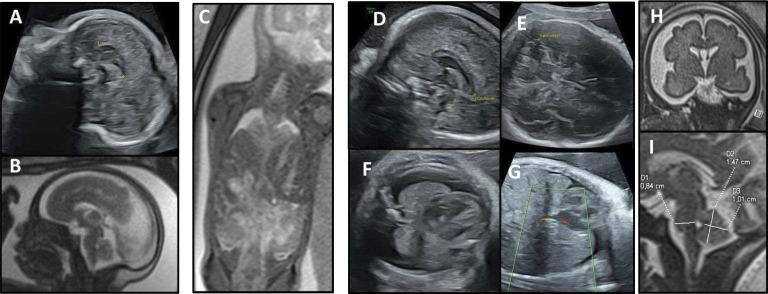

We present a TOKAS antenatal cohort, describing 11 new cases in 6 French families. We report a high frequency of diaphragmatic hernia (9 of 11), differences in sex development (10 of 11) and various visceral malformations. We report some recurrent dysmorphic features, but also pontocerebellar hypoplasia, pre-auricular skin tags and olfactory bulb abnormalities previously unreported in the literature. Although no clear genotype-phenotype correlation has yet emerged, we show that a recurrent p.(Arg611Cys) variant accounts for 66% of fetal TOKAS cases. We also report two new likely pathogenic variants in , outside of the two previously known mutational hotspots.

Overall, we present the first fetal cohort of TOKAS, describe the clinical features that made it a recognisable syndrome at fetopathological examination, and extend the phenotypical spectrum and the known genotype of this rare disorder.